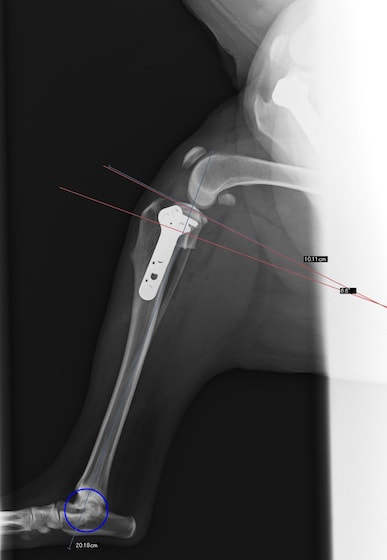

HPの外科の「その他の整形外科疾患」のページに、犬の足根関節の部分関節固定術を追加致しました。(コチラ)足根関節は脛骨、腓骨、踵骨、距骨、足根骨、中足骨と複数の骨で形成され、その関節構造は複雑であり複数の靭帯と腱で安定化されています。足根関節の脱臼や亜脱臼は、主に落下や激しい運動中の外傷によって生じます。症状として、患部は熱感を持って腫れ、動物は痛みにより後肢を挙上したり、負重を避けるように行動します患部g腫れ、動物は痛みにより歩行時や排泄時に体重がかからないように庇。治療法は、軽症の場合は副子や装具による保存療法を行いますが、重症の場合は靭帯修復や関節を固定する関節固定術を行う必要があります。歩行異常や足を庇うような仕草が認められる場合はお早めにご相談下さい。

獣医師 臼井